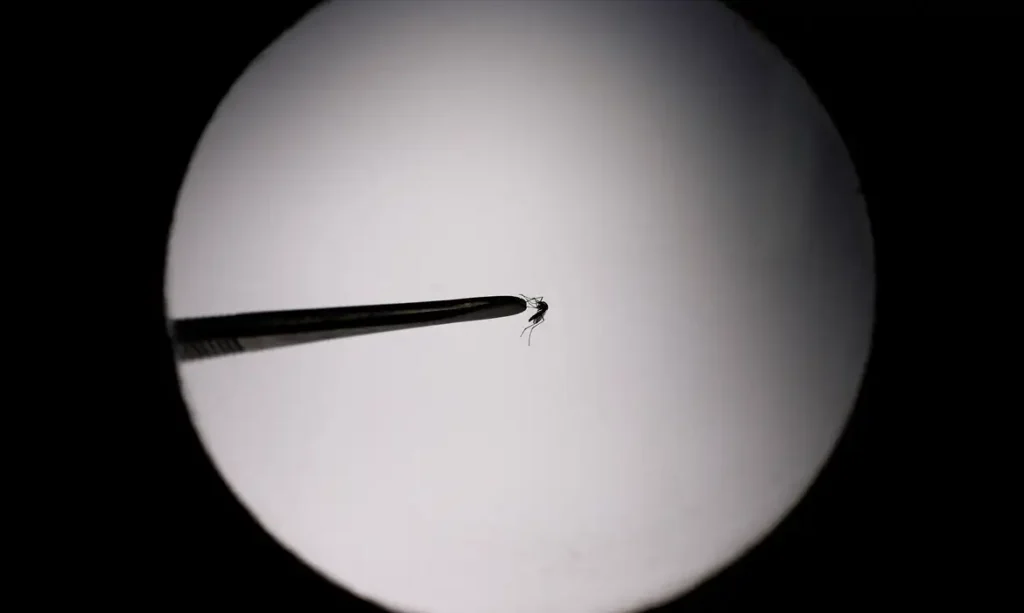

Outros 273 óbitos estão sendo investigados para saber se são decorrentes da dengue O Brasil já registra, apenas neste ano, um total de 392.724 casos prováveis de dengue, de acordo com números divulgados pelo Ministério da Saúde nesta quarta-feira (7). O ministério também confirmou 54 mortes pela doença no país. Outros 273 óbitos estão sendo investigados para saber se são decorrentes da dengue. De acordo com o Painel de Monitoramento do ministério, a população feminina representa 54,9% dos casos, enquanto pessoas do sexo masculino somam 45,1%. Mais de 143,2 mil dos casos prováveis estão concentrados na população entre 30 e 49 anos de idade. A explosão de casos de dengue em diversas regiões do país fez com que ao menos quatro estados – Acre, Minas Gerais e Goiás –, além do Distrito Federal, decretassem situação de emergência em saúde pública. O município do Rio de Janeiro também está em situação de emergência. Estima-se que o Brasil pode contabilizar mais de 4,1 milhões de casos em 2024. Com 135.716 casos prováveis, Minas Gerais é o estado com mais diagnósticos da arbovirose. Em seguida, aparecem São Paulo (61.873), Distrito Federal (48.657), Paraná (44.200) e Rio de Janeiro (28.327). Na análise do coeficiente de incidência por 100 mil habitantes, a capital federal lidera com 1.727,2 casos por 100 mil habitantes. Em seguida estão Minas Gerais (660,8) e o Acre (539,1). A grave situação vivida pelo DF deve fazer antecipar o início da vacinação para esta sexta-feira (9), informou o governo local. A capital federal vai receber um total de 194 mil doses da vacina. Em todo o país, as doses estão sendo distribuídas para 521 municípios selecionados pelo Ministério da Saúde para iniciar a vacinação na rede pública. As cidades compõem um total de 37 regiões de saúde que, segundo a pasta, são consideradas endêmicas para a doença. Serão vacinadas crianças e adolescentes de 10 a 14 anos de idade, faixa etária que concentra maior número de hospitalizações por dengue, atrás apenas dos idosos. CONTINUA DEPOIS DA PUBLICIDADE Em pronunciamento à nação na noite dessa terça-feira (6), a ministra da Saúde, Nísia Trindade, fez um apelo para que a população adote cuidados para evitar a proliferação de criadouros do mosquito transmissor da dengue dentro de casa. Segundo a ministra, 75% dos focos estão localizados nas residências. As informações são da Agência Brasil.